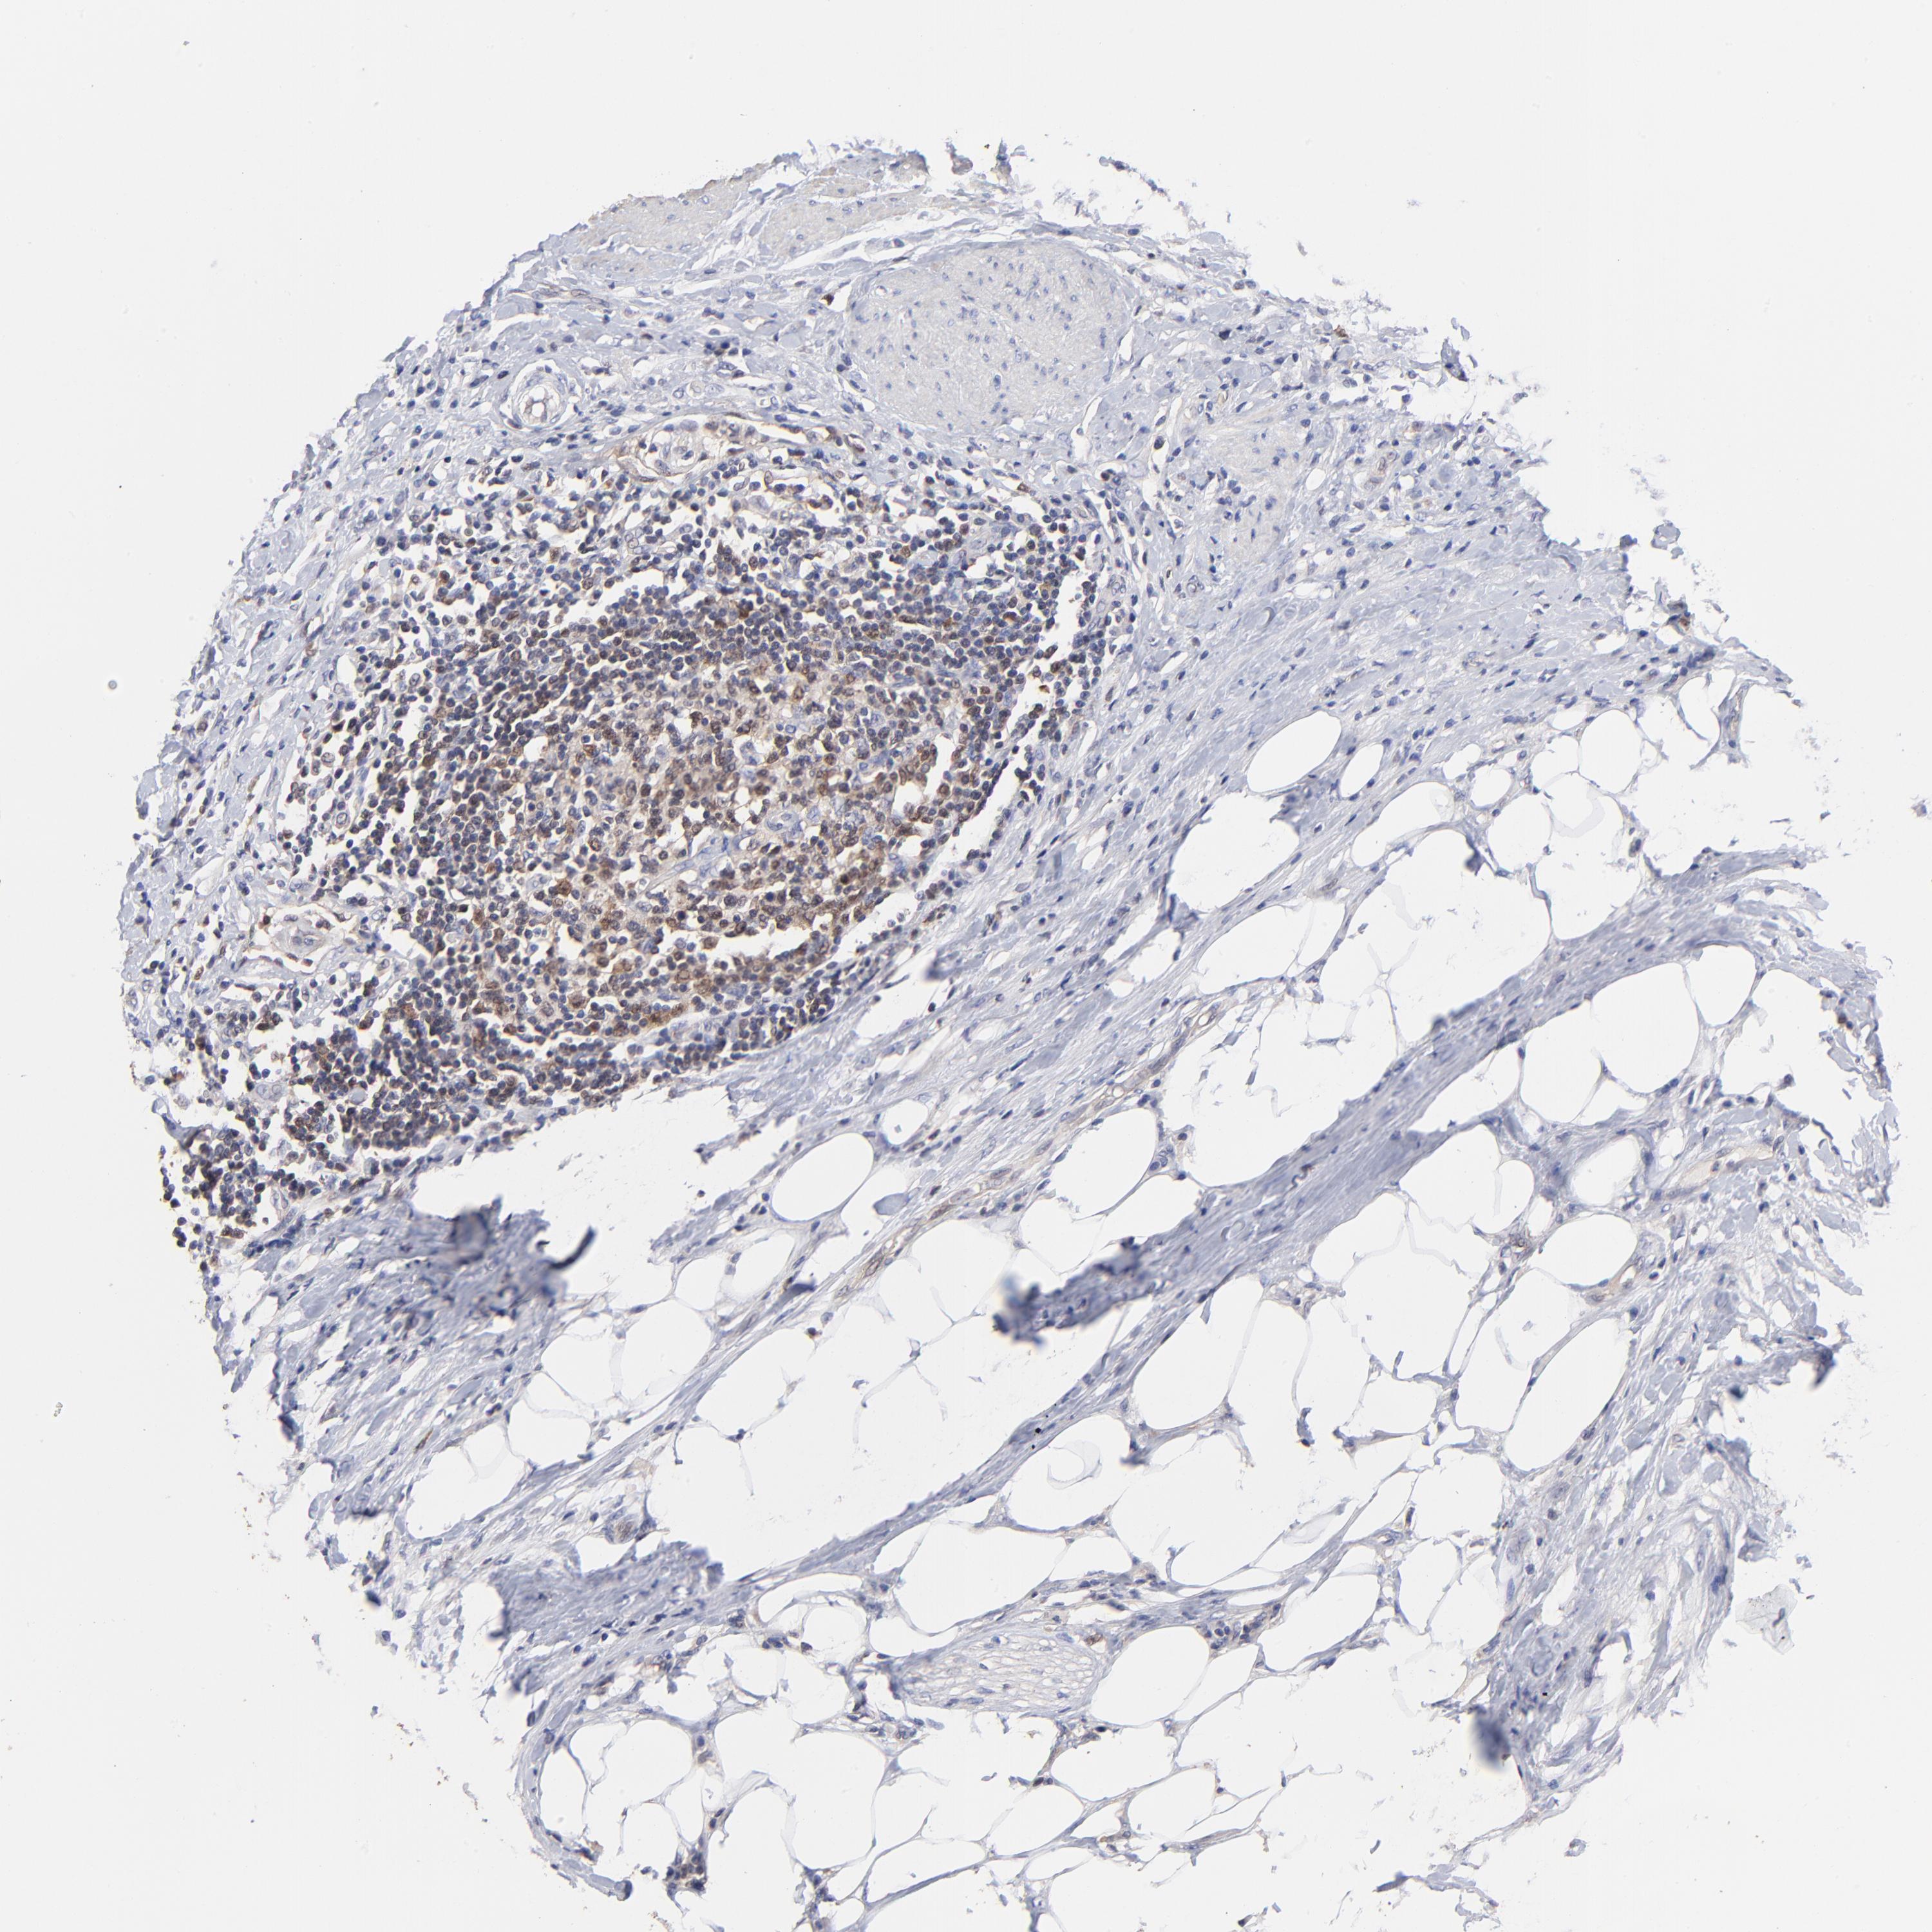

UROTHELIAL CANCER - Protein expressioni

A mouse-over function shows sample information and annotation data. Click on an image to view it in a full screen mode. Samples can be filtered based on level of antibody staining by selecting one or several of the following categories: high, medium, low and not detected. The assay and annotation is described here.

Antibody stainingi

Antibody staining in the annotated cell types in the current human tissue is reported as not detected, low, medium, or high, based on conventional immunohistochemistry profiling in selected tissues. This score is based on the combination of the staining intensity and fraction of stained cells.

Each image is clickable and will lead to virtual microscopy that enables deeper exploration of all samples and also displays staining intensity scores, fraction scores and subcellular localization as well as patient and tissue information for each sample.

Antibody HPA002832

Staining

High

Medium

Low

Not detected

Intensity

Strong

Moderate

Weak

Negative

Quantity

>75%

75%-25%

<25%

None

Location

Nuclear

Cytoplasmic/membranous

Cytoplasmic/membranous,nuclear

Urothelial carcinoma, High grade

Urothelial carcinoma, Low grade